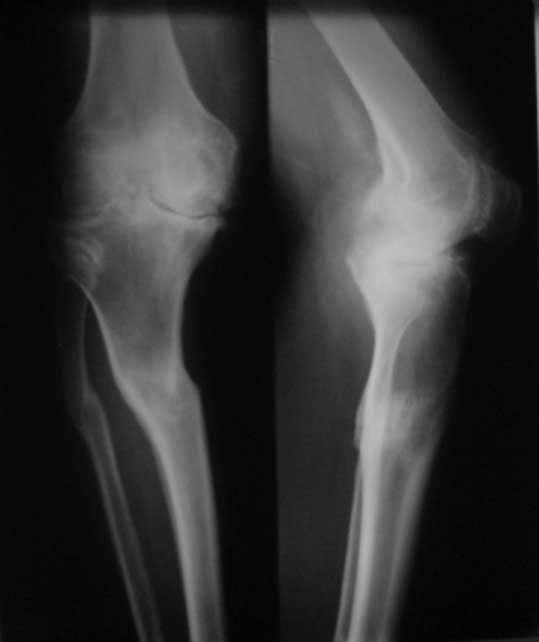

Уважаемые коллеги. Пациент 8 мес после операции ТКА, в анамнезе – неправильно сросшийся перелом голени, коррекция оси (снимки прилагаются. В настоящее время имеется разгибательная контрактура 10/5/0, на операционном столе было 90/0/5, на момент выписки движения 50/0/0 в надежде на дальнейшую разработку. До эндопротезирования 40/10/0. Глубокая инфекция исключена. Ротация бедренного компонента в норме (по КТ).

Вопросы: насколько для такого ограничения критична некорректная установка б/б компонента (я намерял 7 град)? Причина нынешнего состояния, артрофиброз? Какие действия следует предпринять, удаление рубцов, релиз головок 4-главой мышцы? Что-либо другое, ваше мнение?